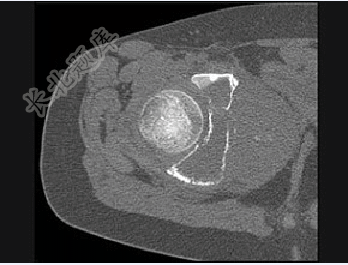

- 单项选择题男,15岁,右髋部疼痛、红肿,有压痛,皮温增高,结合图像,最可能的诊断是( )

A、Ewing肉瘤

B、急性骨髓炎

C、转移性神经母细胞瘤

D、骨肉瘤

E、骨结核